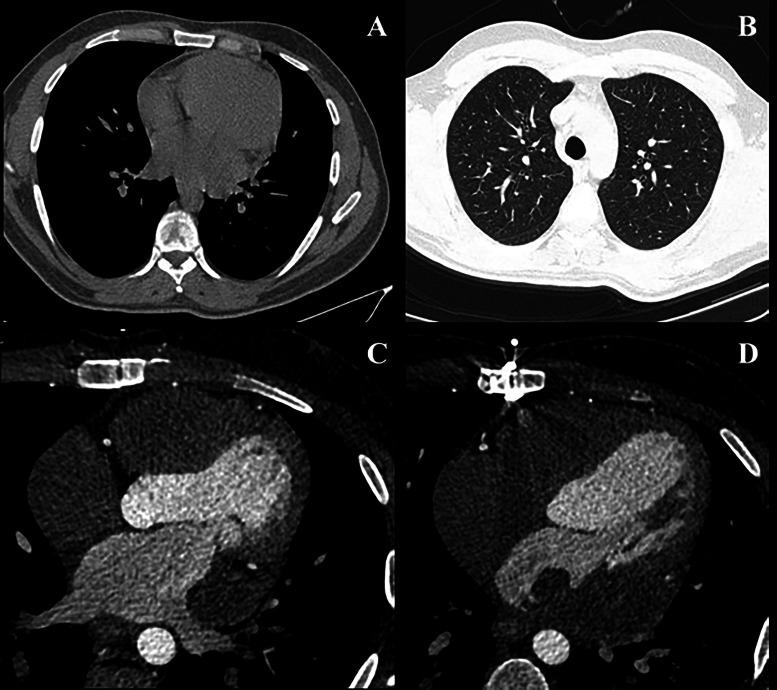

Undifferentiated pleomorphic cardiac sarcomas are extremely rare, highly malignant mesenchymal cardiac neoplasms typically presenting in the sixth decade of life. Here, we have reported a rare case of undifferentiated pleomorphic cardiac sarcoma presenting with dyspnea in a young male. On further evaluations, a large, ill-defined, multilobulated mass was observed in left atrium (LA) with encasement of left circumflex artery, attachment to mitral valve annulus, and invasion through LA wall and pericardium.

未分化多形性心脏肉瘤极为罕见,是一种高度恶性的间质性心脏肿瘤,通常在60岁左右出现。在此,我们报告了一例罕见的未分化多形性心脏肉瘤,该病例为一名年轻男性,表现为呼吸困难。进一步评估发现,左心房(LA)有一个大的、边界不清的多叶状肿块,包绕左旋支动脉,附着于二尖瓣环,并侵及左心房壁和心包。